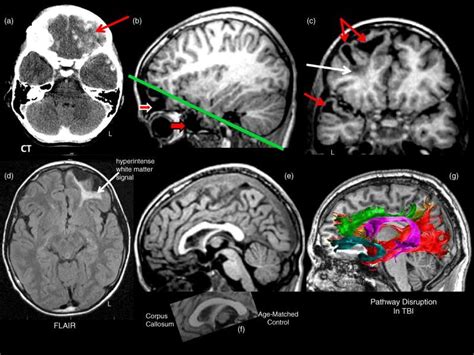

Traumatic Brain Injury CT Scan

Mild Traumatic Brain Injury MRI